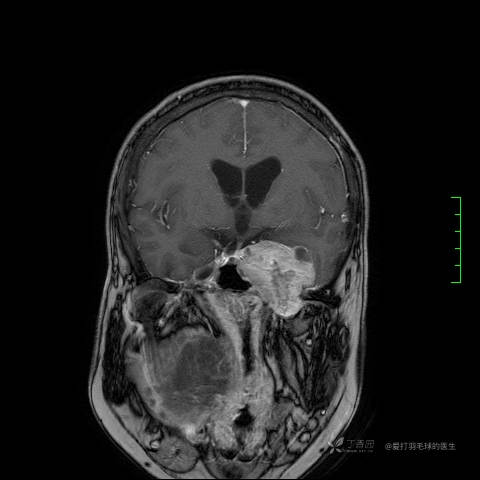

主诉:患者因反复右侧腰痛伴右下肢麻木2年余入院。

简要病史:自诉右甲状腺功能亢进症多年,规律服药,平素多有心悸、胸闷、活动后明显。既往腰椎椎管内肿瘤切除术。